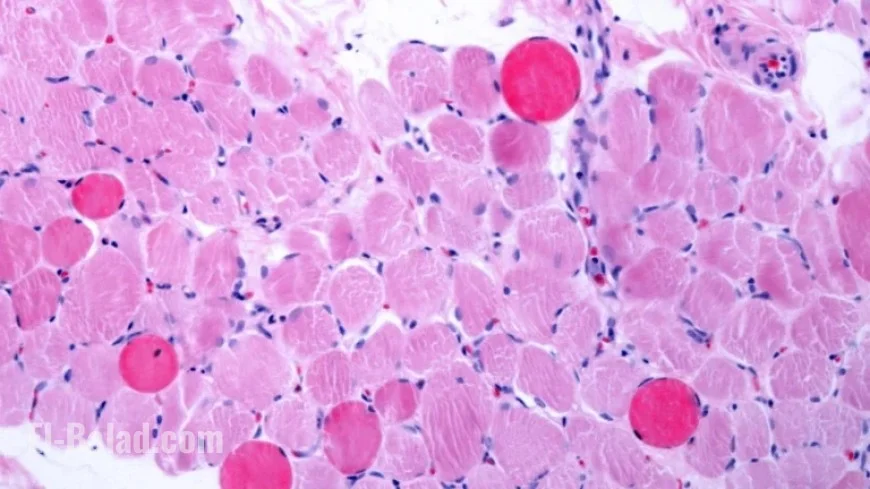

Capricor Therapeutics has announced significant progress in treating Duchenne muscular dystrophy through its innovative cell therapy. The company revealed that its treatment improved heart and muscle function in patients, achieving the primary objectives of a Phase 3 clinical trial.

• Duchenne muscular dystrophy is a severe muscle degenerative condition.

• Capricor’s therapy, deramiocel, has shown promising improvements in heart and muscle function.